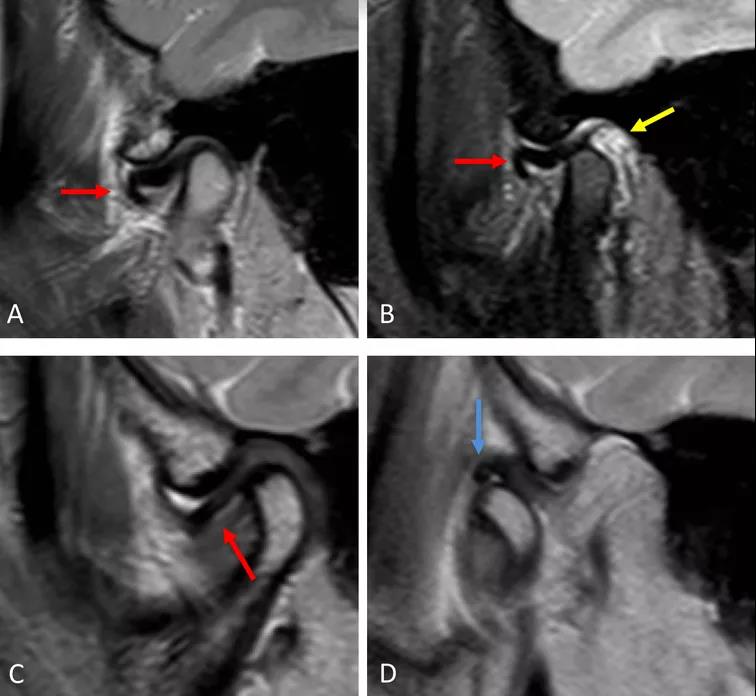

病例一:斜矢狀平面上的質(zhì)子密度加權圖像(PDWI)

A圖示:閉口位時,顯示關節(jié)盤前移位明顯,雙凹形態(tài)消失。注意前帶的下移位(紅色箭頭)。

B圖示:張口位時,顯示關節(jié)盤移位(紅色箭頭),關節(jié)積液(黃色箭頭)。病例2:斜矢狀平面上的質(zhì)子密度加權圖像(PDWI)